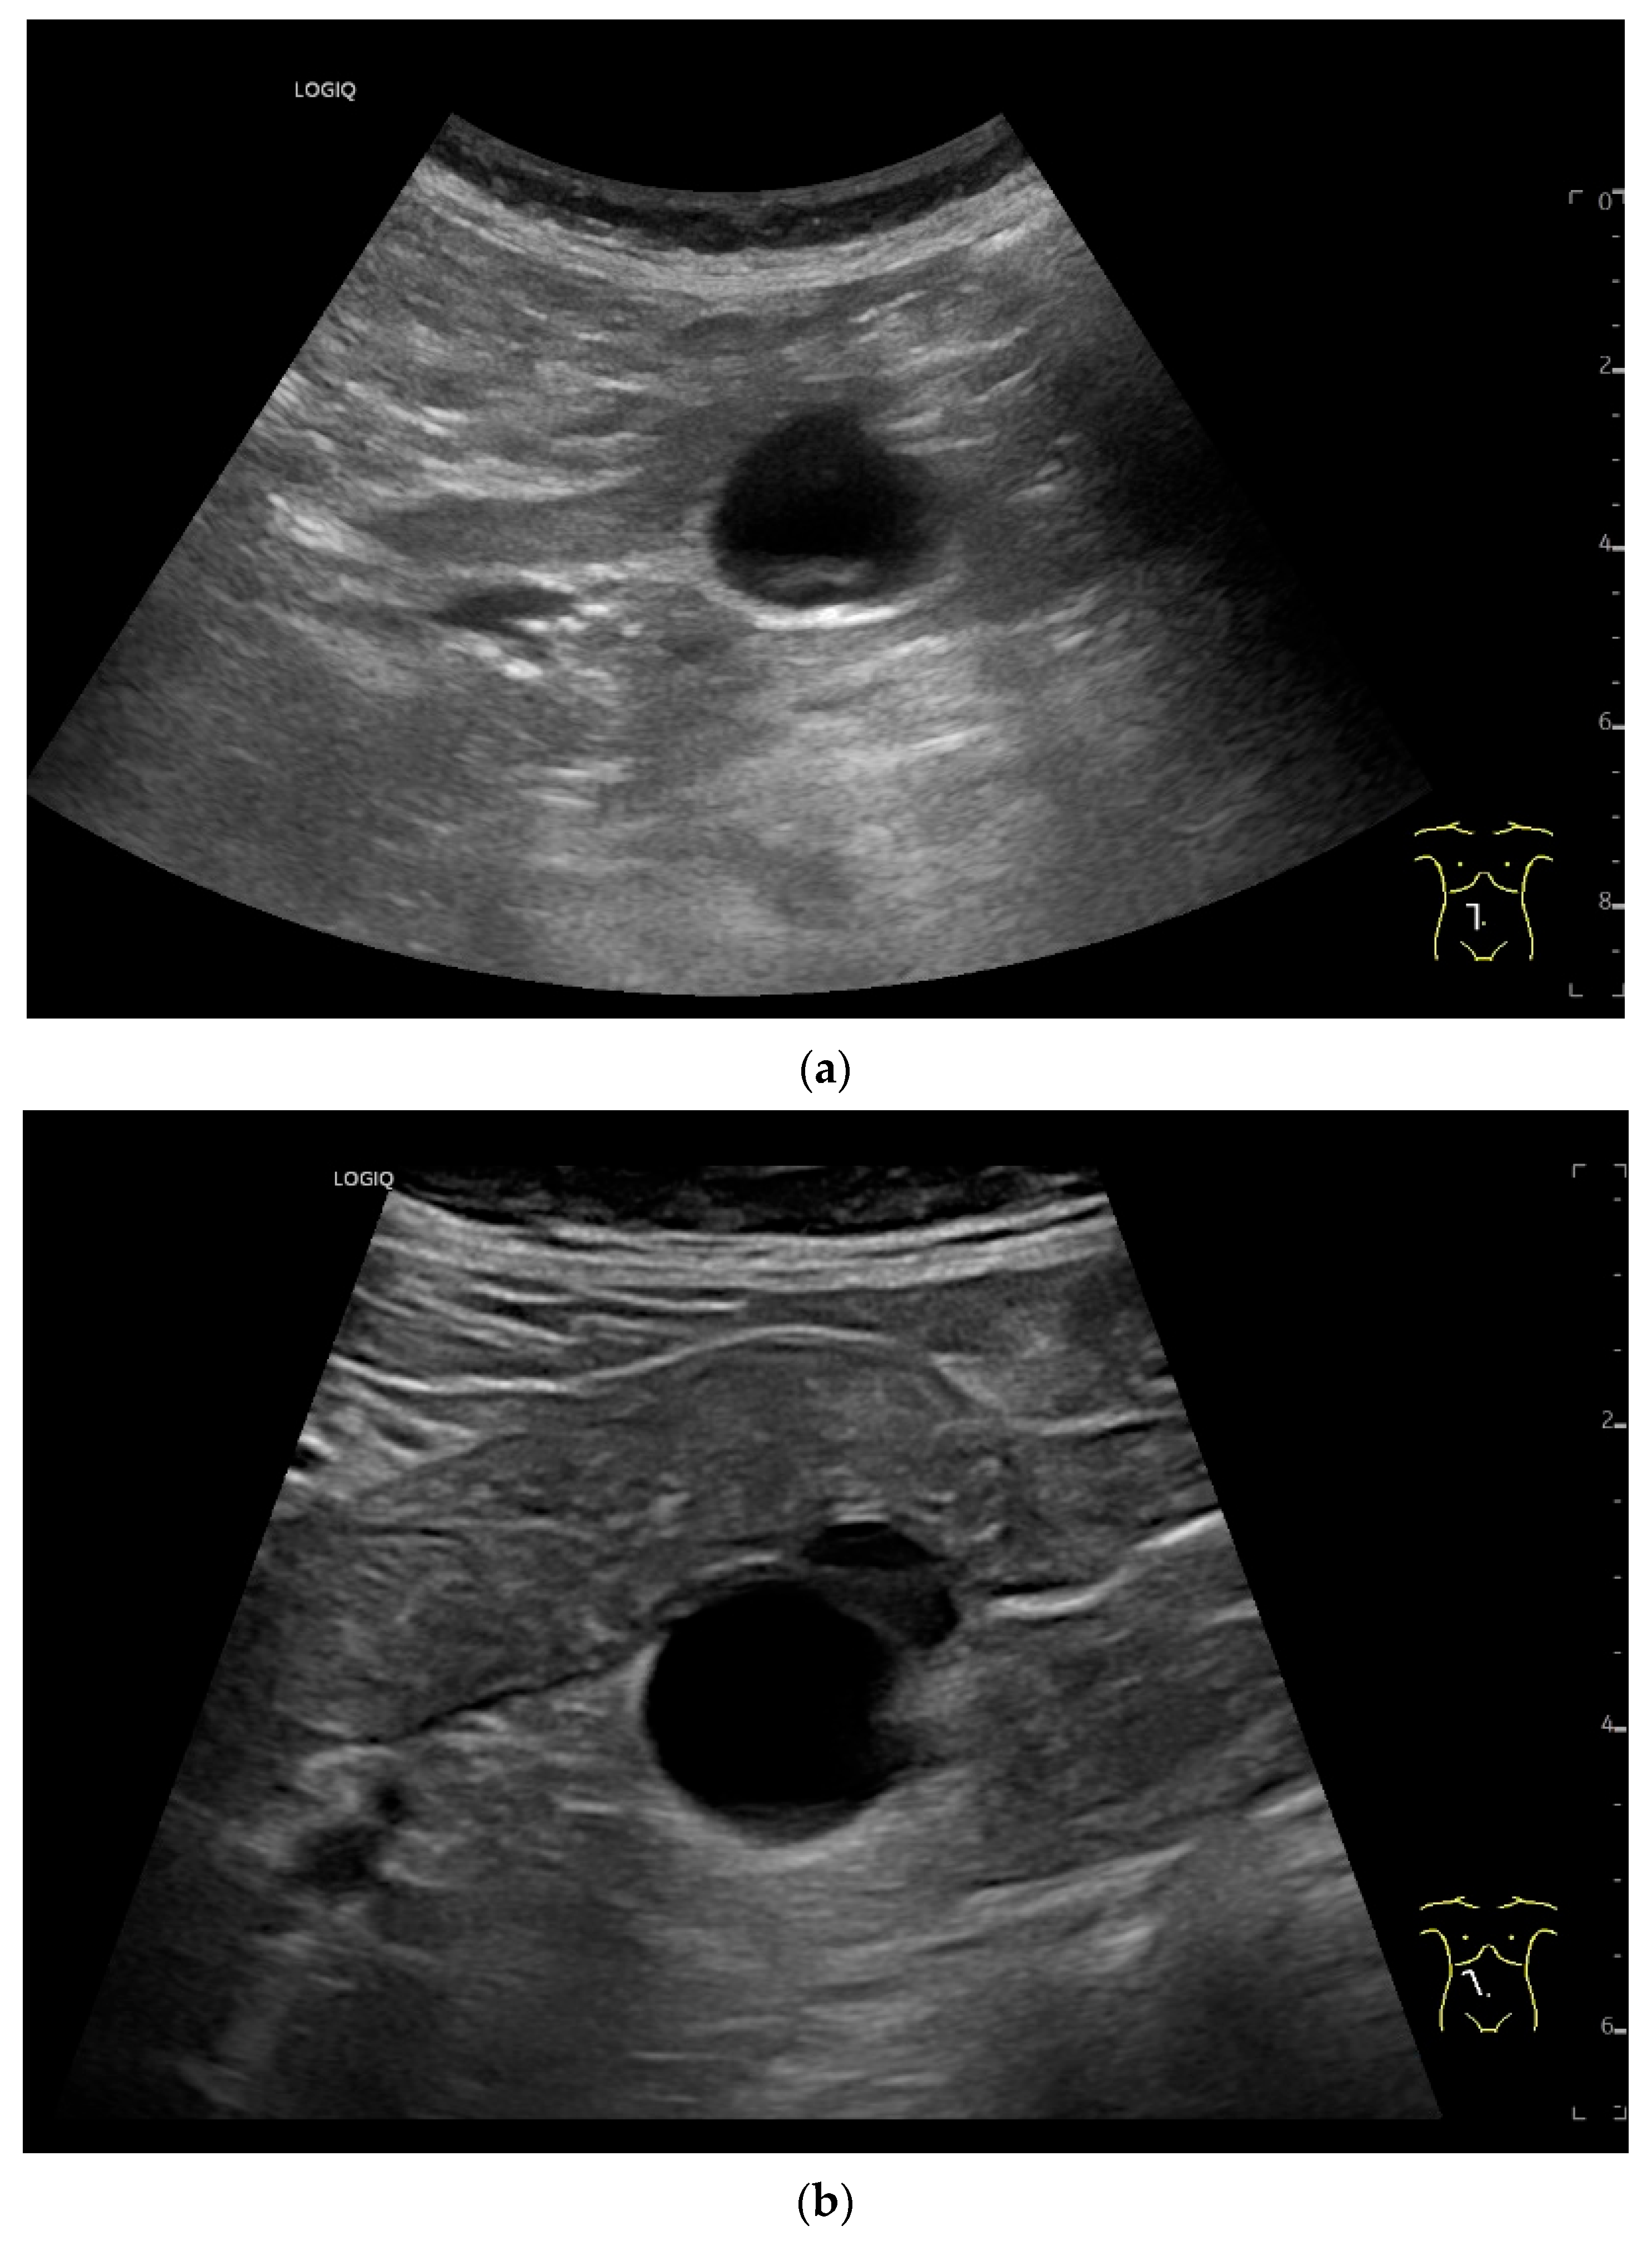

- Hasegawa, T.; Sumimura, J.; Mizutani, S.; Tazuke, Y.; Okuda, S.; Dezawa, T. The doughnut sign: An ultrasound finding in pediatric intestinal Burkitt’s lymphoma. Pediatr. Surg. Int. 1998, 13, 297–298. [Google Scholar] [CrossRef] [PubMed]

| Lymphangioma | Anechoic cystic lesions related to the small intestine wall. No vessels on CDI, Nonenhancement on CEUS. They move with the small intestine. |

| Intussusception | The small intestine proximal to the tumor is invaginated. More than five wall layers are seen in an onion-skin shape. |